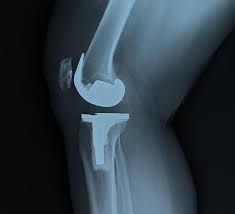

Knee Replacement in Adilabad

At Varunam Hospital, Adilabad, we specialize in advanced knee replacement surgeries to restore mobility and relieve pain caused by severe knee conditions. Whether due to osteoarthritis, rheumatoid arthritis, or injury, our expert orthopedic surgeons are committed to providing the best care possible. Using state-of-the-art technology and minimally invasive techniques, our knee replacement procedures ensure faster recovery times and reduced discomfort.